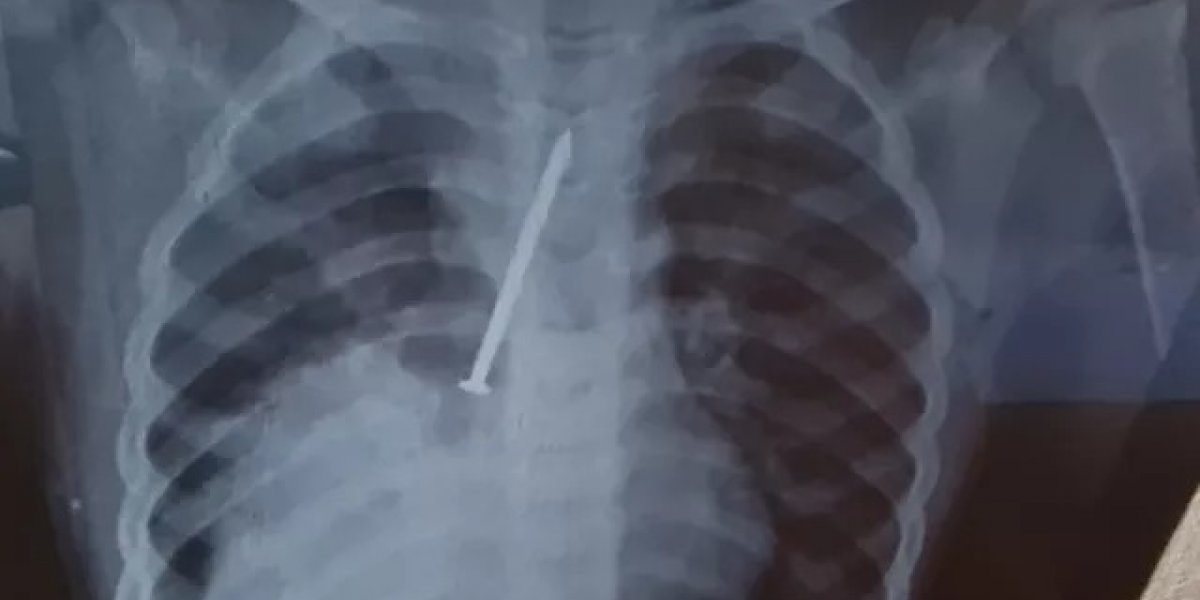

O Conselho Regional de Medicina do Estado da Bahia (Cremeb) vai abrir uma investigação para apurar a conduta dos médicos que atenderam o pequeno Cauan Araújo Conceição, de 3 anos, do município de Canavieiras, no extremo-sul da Bahia, que morreu após passar um ano com um prego no pulmão.

Cauan morreu com uma broncopneumonia, decorrente da presença do prego no corpo. A criança foi levada pelos pais durante o período de um ano para o Hospital Municipal. Só após a realização de exame de Raio-X, na rede particular, o objeto foi localizado no corpo da criança. A Secretaria de Saúde de Canavieiras também já afirmou que iniciou um levantamento para investigar a postura dos médicos nos atendimentos à criança. Já a Polícia Civil apura se houve negligência médica.